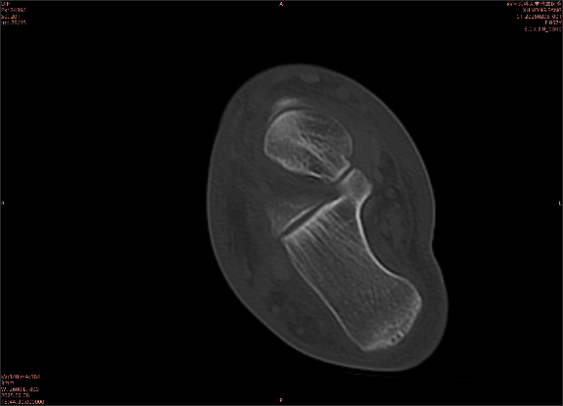

舉例圖像

圖2

專(zhuān)業(yè)解釋看不懂沒(méi)關(guān)系,大家看圖1和圖2就可以了,這是同一個(gè)患者跟骨的磁共振和CT圖像,圖1的紅色箭頭指示的黑線就是磁共振圖像顯示的骨折線,一目了然。而對(duì)比圖2的CT圖像上并未顯示異常。